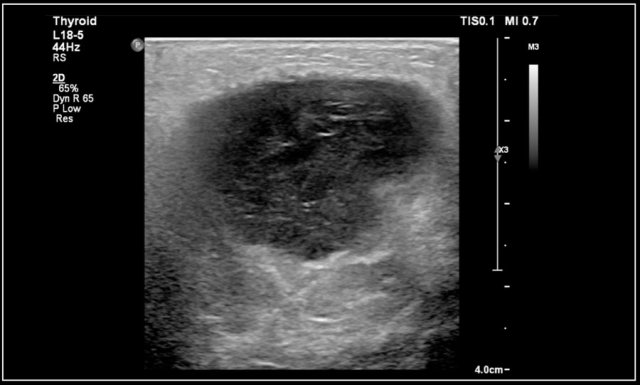

Thyroiditis

The most common forms of thyroiditis are Hashimoto's thyroiditis and Graves disease.

Both Hashimoto's thyreoiditis and Graves disease can present as an enlarged and hyperemic thyroid.

Hashimoto's thyroiditis or chronic lymphocytic thyroiditis is an auto-immune disease.

It presents with hypothyroidism.

Although primarily a disease of the middle-aged it can present in children.

On ultrasound the gland is diffusely enlarged and inhomogeneous.

On color doppler the blood flow is often normal but can be increased like in Graves' disease.

In a later stage the gland shrinks.

Here an image of a 16-year-old girl with hyperthreoidism.

A diffusely enlarged thyroid gland is seen with hyperemia.

The final diagnosis was Graves disease.

She was treated with I-131.